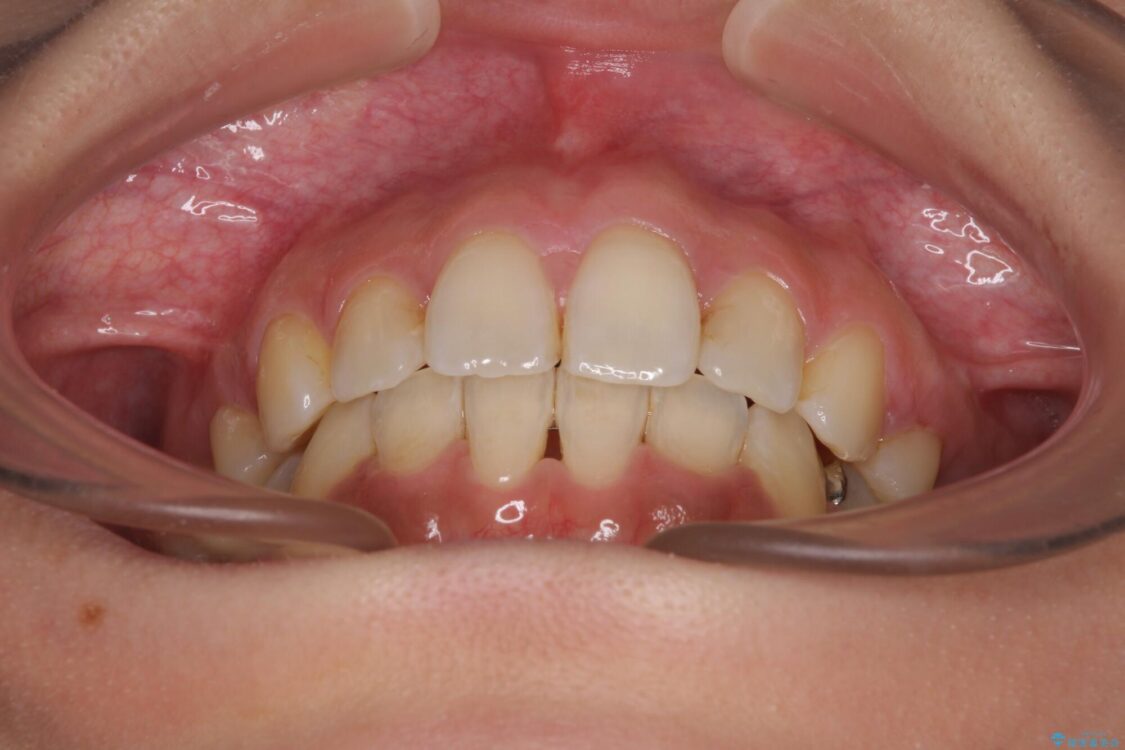

治療後

• デコボコと口元の突出感 ハーフリンガルでの抜歯矯正 治療後画像

治療後について

表側のワイヤー矯正に比べると治療期間は長く、費用も高額となりますが、どうしても目立たせたくないという方にはお勧めの抜歯矯正です。